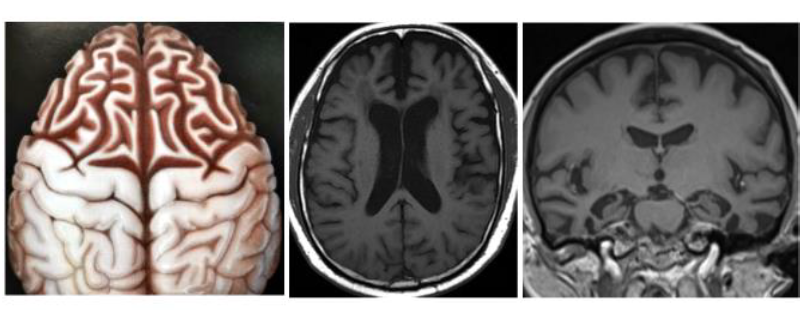

(3) 磁振造影術(MRI):既可直接看到全腦構造(圖四),又可看見阿茲海默症易損部位,如:海馬迴的萎縮及皮質變薄等(圖五)。可同時提供較完整的信息,所以成為目前失智症最重要的篩檢與診斷工具。

(圖五)腦部三種切面,紅色區域即為海馬迴位置。│ NeuroImage: Clinical 11 (2016) 435-49